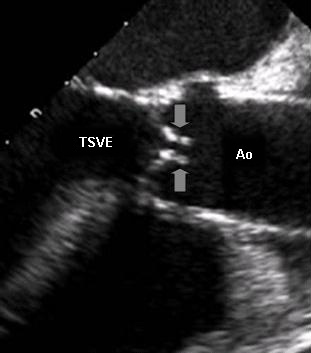

A ETE fornece visões alternativas detalhadas do aparato valvar aórtico e é frequentemente usada em pacientes submetidos a cirurgia valvar ou substituição transcateter da valva aórtica.[29][Figure caption and citation for the preceding image starts]: Ecocardiografia transesofágica mostrando a via de saída do ventrículo esquerdo (VSVE), a aorta (AE) e folhetos quase imóveis (setas) de valva aórtica gravemente estenóticaDo acervo de Dr. David Liff, MD, Emory University Hospital; usado com permissão [Citation ends].